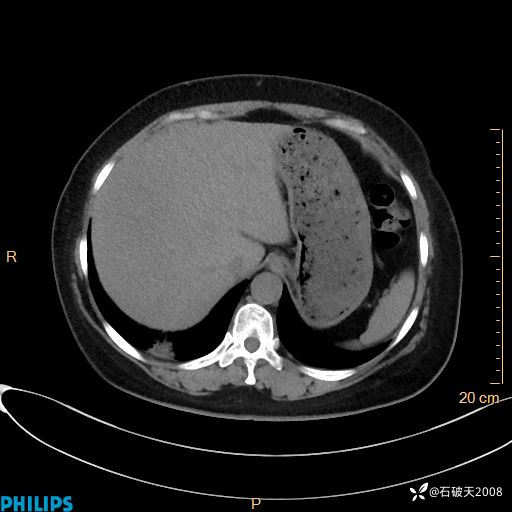

动脉期